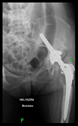

The radiological examination allowed us to verify the close bone-to-implant contact and the unchanged position of the implant during follow-up.

In all the cases operated with the above-described targeting procedure, the stems of the cups remained between the cortical bone surfaces without perforation of the linea terminalis, as shown by postoperative radiographs. There were no complicated surgical situations. In 16 cases, the wound healings were uneventful, and the hips were able to bear weight again after postoperative rehabilitation.